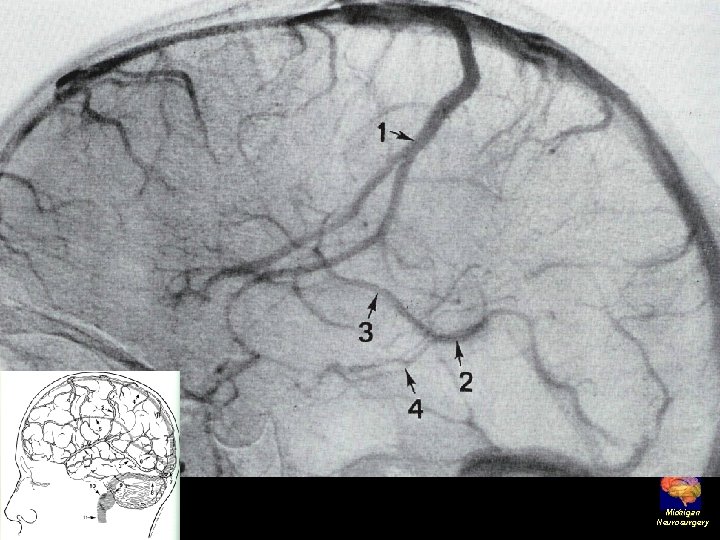

Superficial Veins • Sylvian vein • Vein of Trolard • Vein of Labbe • Cortical veins draining into the dural sinuses Michigan Neurosurgery

Angiographic digression to aid the understanding of venous angiography Michigan Neurosurgery